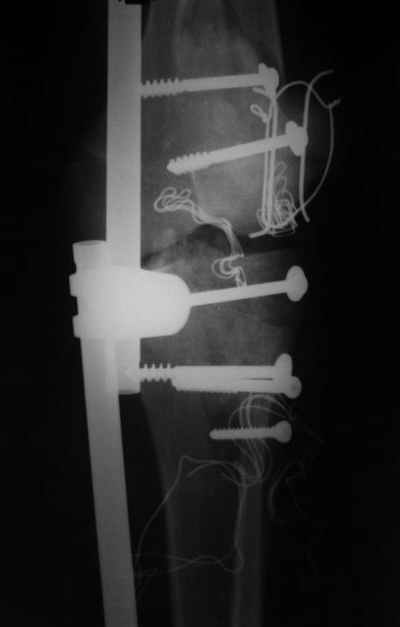

Re: открытый перелом мыщелков бедра, латерального

Evgueny Tschekashkin 14 Декабрь 2004, 18:41

Вид раны на сегодня...

4 cутки после травмы.